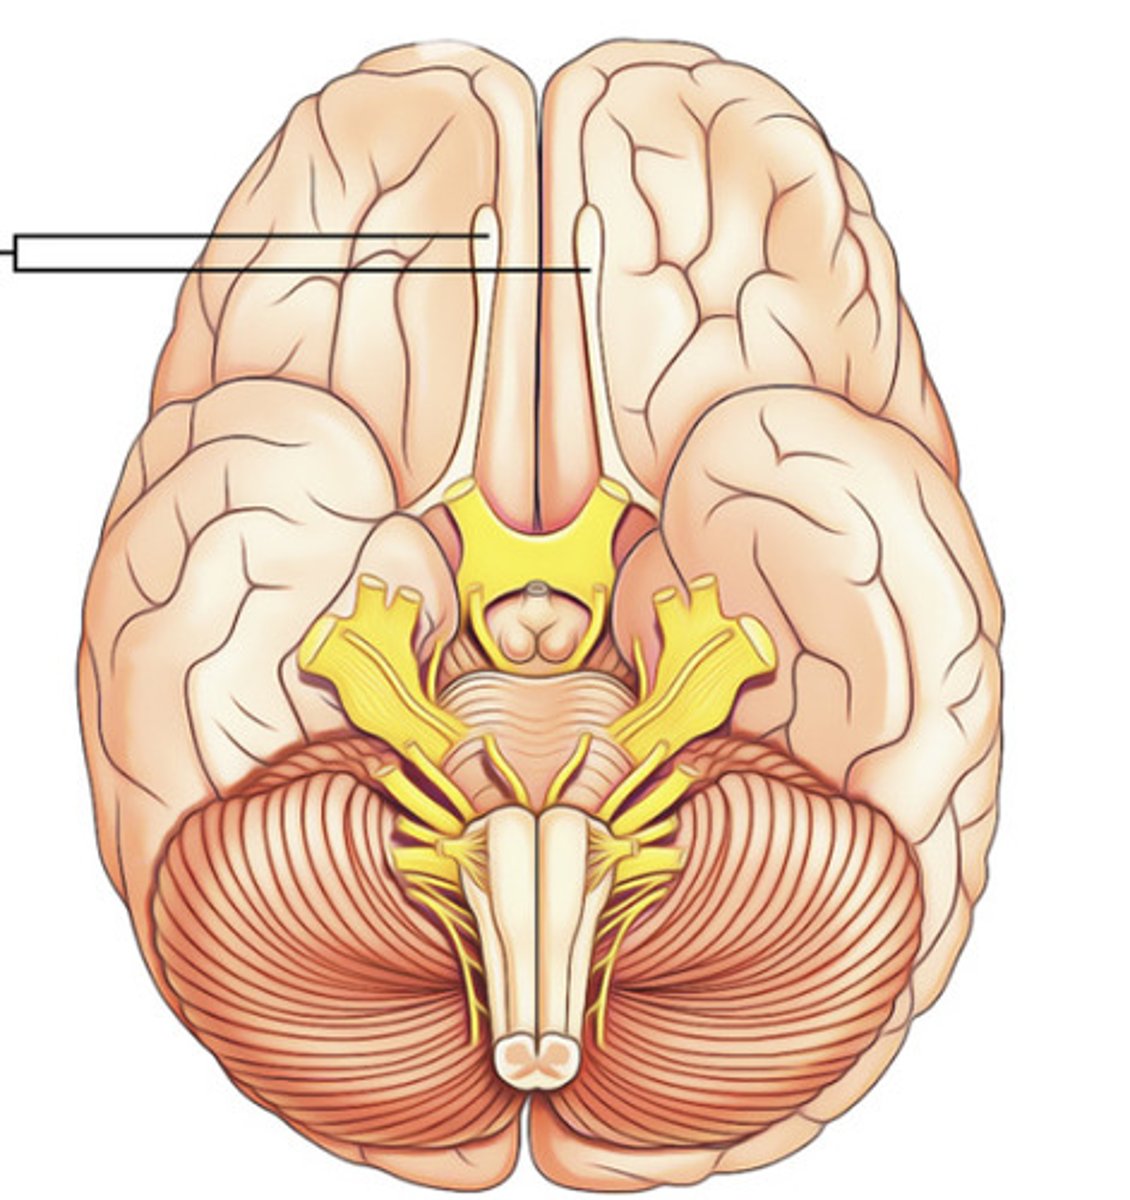

1 smell

Olfactory Nerve

2 vision

Optic Nerve

3 controls superior rectus, inferior rectus, medial rectus, & inferior oblique muscles moving the eye

Oculomotor Nerve

4 controls superior oblique eye muscle

Trochlear Nerve

5 Major sensory nerve of face, controls muscles in mastication (chewing)

Trigeminal Nerve

6 controls lateral rectus muscle of eye

Abducens Nerve

7 controls muscles of facial expression, sense of taste

Facial Nerve

8 sense of equilibrium and hearing

Vestibulocochlear Nerve

9 controls pharyngeal muscles & salivary glands, sense of taste

Glossopharyngeal Nerve

10 largest parasympathetic nerve

Vagus Nerve

11 controls neck muscles

Accessory Nerve

12 controls muscles of tongue

Hypoglossal Nerve

Olfactory Bulb & Tract

-sense of smell

-nerve 1

Optic Nerve & Optic Chiasm

-vision

-nerve 2

Oculomotor Nerve

-controls eye movement

-nerve 3

Trigeminal Nerve

-big nerve w/ 3 branches,

-sensation from face and controls chewing

-nerve 5

(sometimes hides the occulomotor nerve until moved/removed carefully)

Pons

-bridge that links medulla oblongata to thalamus

Medulla Oblongata

-houses autonomic centers